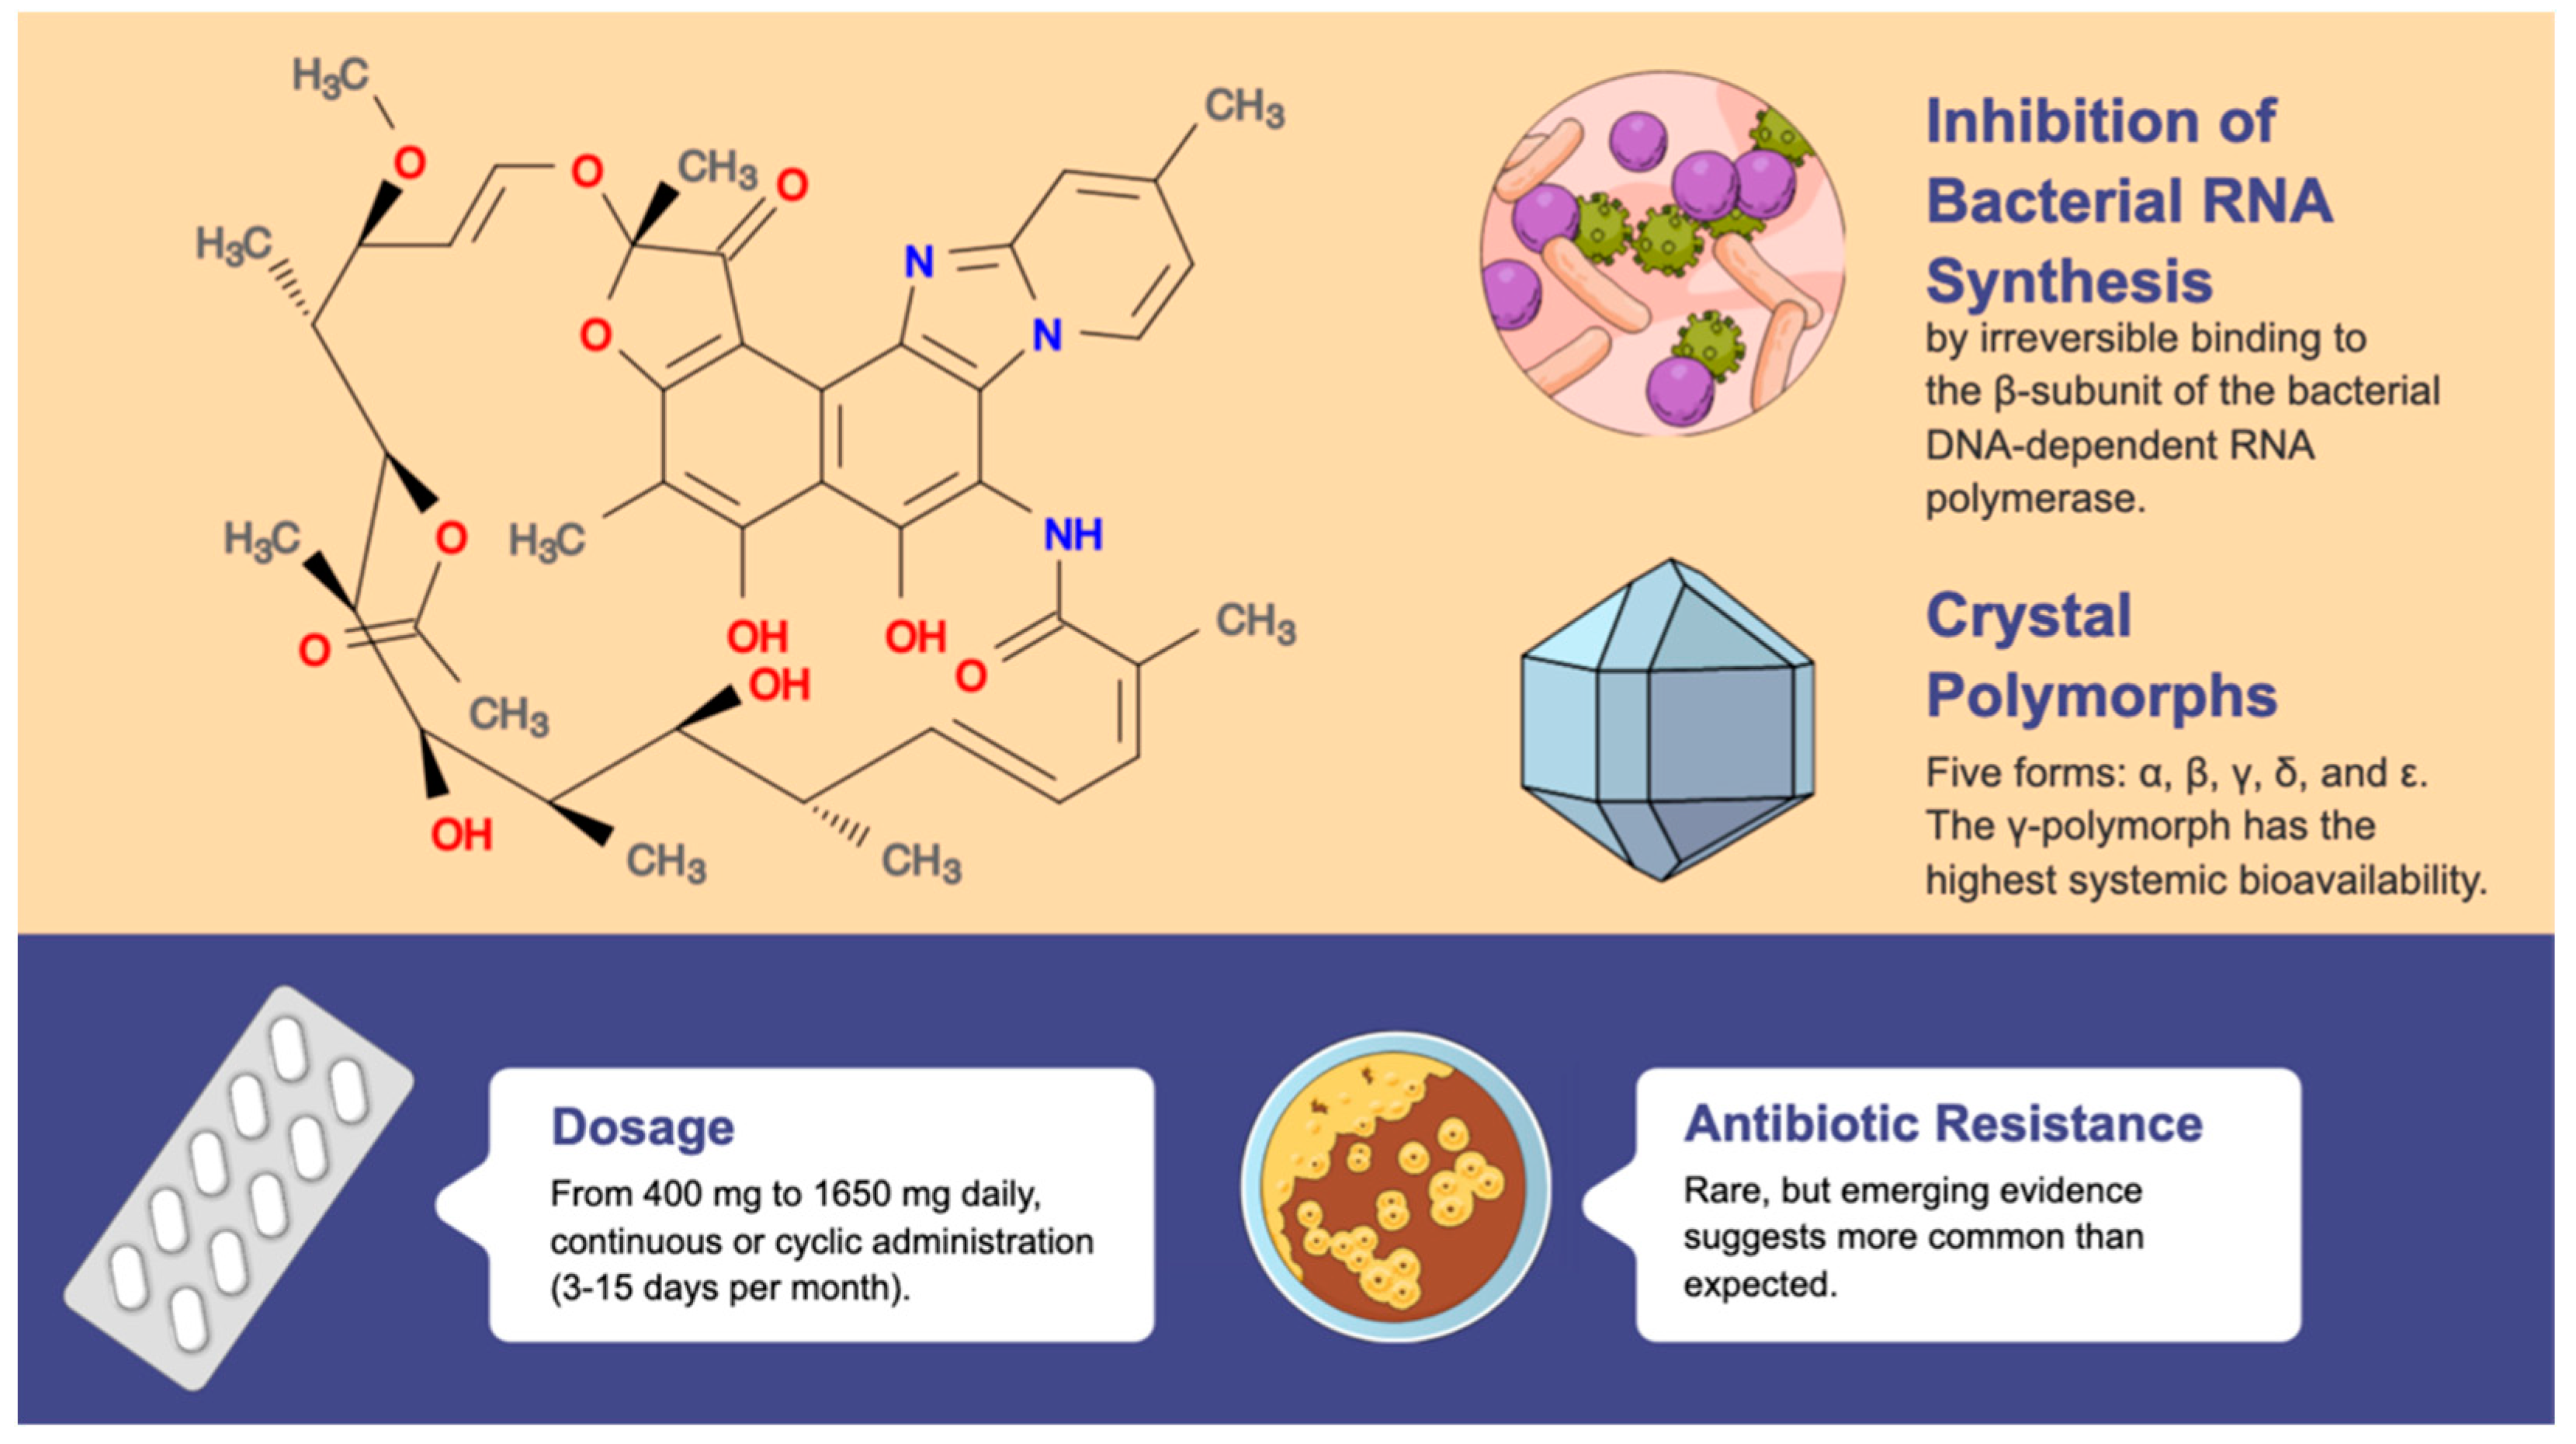

2. Rifaximin

2.1. Indications, Effects, and Therapeutic Strategies

2.2. Long-Term Use and Antimicrobial Resistance